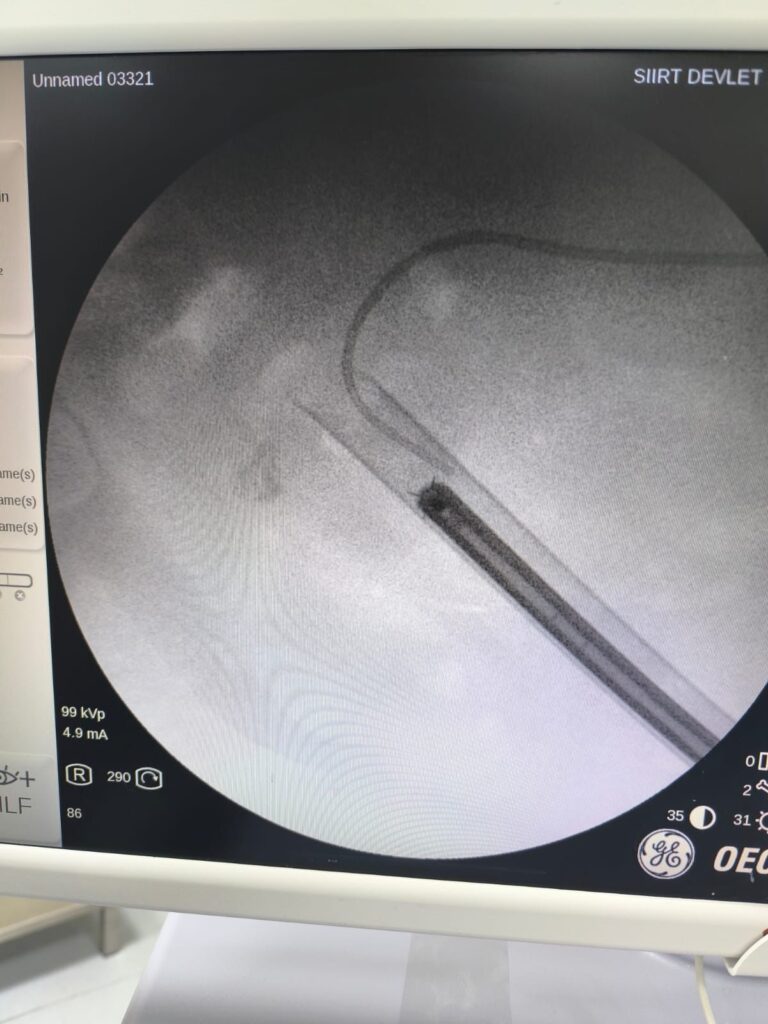

Staghorn taşlar böbreğin tüm boşluklarını doldurup, tekrarlayan enfeksiyonlara ve uzun vadede böbrek fonksiyon kaybına yol açabildiğinden tedavisi hayati önem taşımaktadır. Biz de bu vakamizda, Perkütan Nefrolitotomi (PCNL) yöntemiyle böbreğe küçük bir cilt kesisi üzerinden girerek endoskopik cihazlarla taşları parçalayıp çıkardık. PCNL, özellikle çapı 2 cm’den büyük ve kompleks taşlarda altın standart kabul edilmektedir. Normalde staghorn taşların temizlenmesi uzun süren ve çoğu zaman birden fazla seans gerektiren zorlu bir süreçtir.

Ancak ameliyat ekibimizin deneyimi ve hastanemizin modern altyapısı sayesinde, ciltten tek giriş yolu açılarak yaklaşık 1,5 saatlik bir seansta böbreğin tüm taş yükü başarıyla temizlendi. Ameliyat sonrası süreçte ise, hastamızın iyileşmesinde herhangi bir sorun yaşanmadı ve şifa ile taburculuğu planlandı. Siirt Eğitim ve Araştırma Hastanesi olarak hedefimiz, halkımıza en modern tedavi yöntemlerini sunmak ve bölgemizde sağlık hizmetlerinin gelişimine katkıda bulunmaktır. Son olarak, tedavi sürecinde desteğini esirgemeyen tüm ekip arkadaşlarımıza da ayrıca teşekkür ederim.”